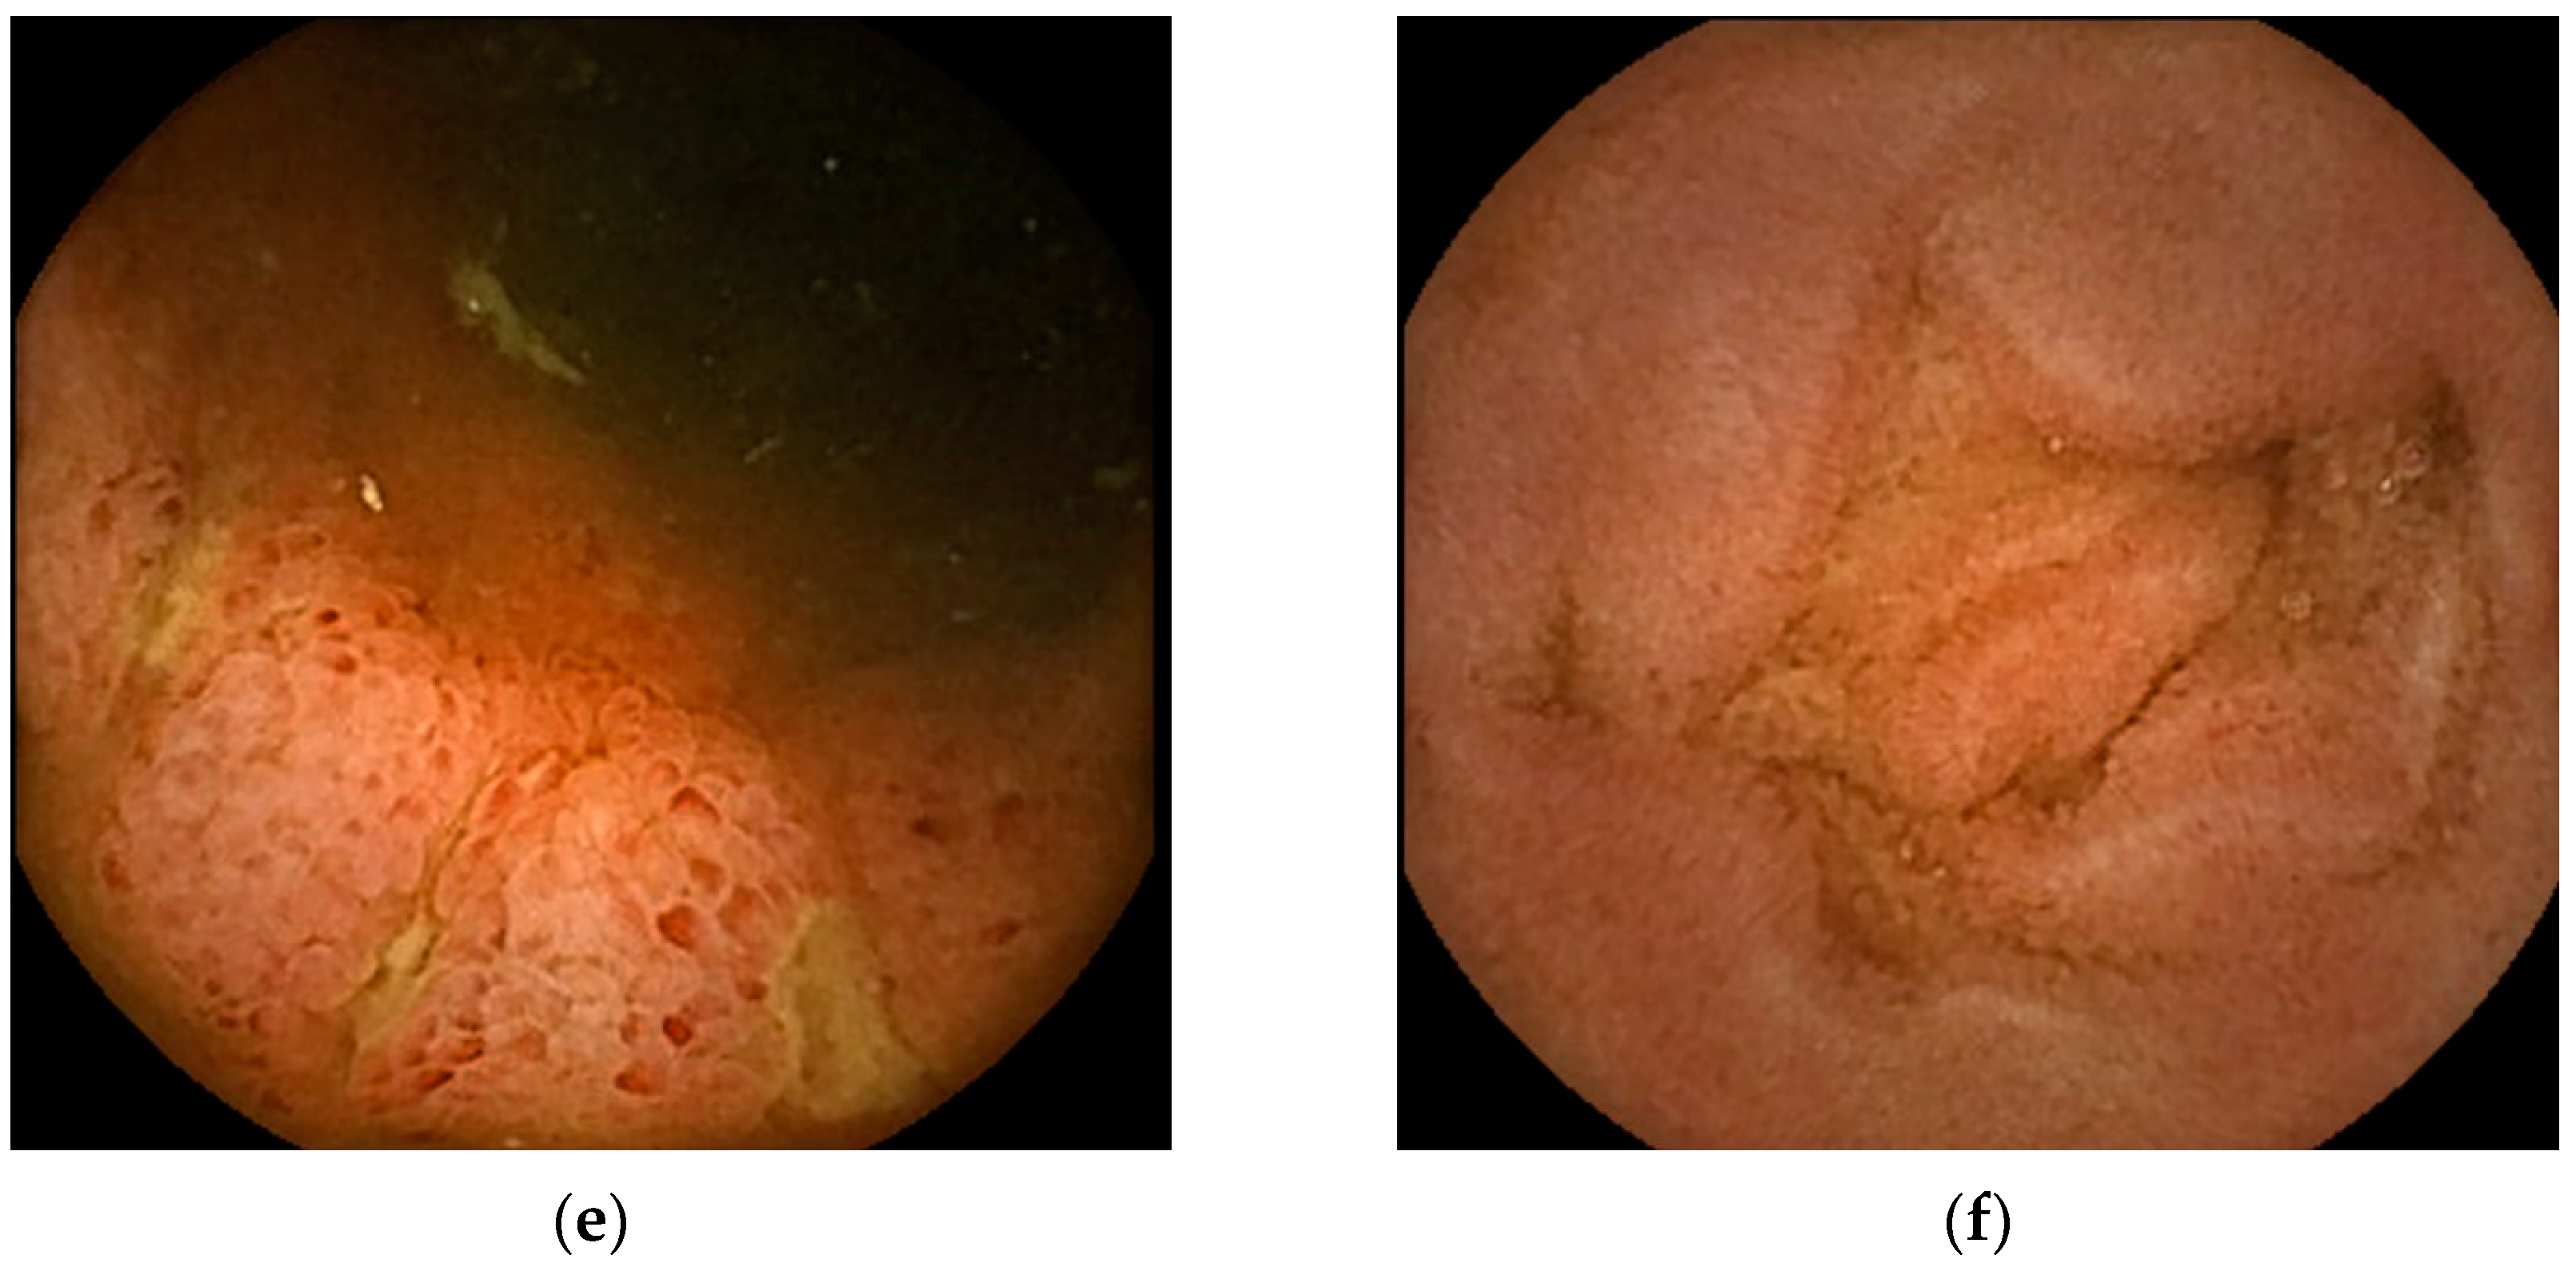

Figure 2.

Representative images of small bowel capsule endoscopy of our own EoGE cases: (a) patchy redness with edema and atrophy; (b) scattered redness with edema; (c) villous atrophy with redness; (d) erosions with surrounding redness; (e) ulcers; (f) edema. All images were captured with PillCamSB3 (Covidien Japan Inc., Tokyo, Japan). EoGE: eosinophilic gastroenteritis.

The second most frequently reported finding was villous atrophy (40.9%; Figure 2c) [14,16,18,21,22,25]. Erosion (Figure 2d) and ulceration (Figure 2e) were the third most frequently reported findings (27.2%). We previously noted that erosions in patients with EoGE are characterized by surrounding redness [24]. Linear ulcers on the terminal ileum [24] or circumferential ulcers [12,19,20,22] have been reported as small bowel ulcers in patients with EoGE. In three of the four reported cases of circumferential ulceration, it was located in the ileum [12,19,22], and stenosis was present in all four cases. Edematous mucosa of the small bowel (22.7%, Figure 2f) has also been documented in patients with EoGE [11,13,15,19]. The few reported cases include mucosal congestion [16], whitish exudate [18], short rounded edematous villi [19], and dark blue coloration of the deeper layers of the terminal ileum [23]. The case in which dark blue coloration was observed was a serosal-type EoGE, suggesting that this finding may have captured submucosal changes in the small bowel.